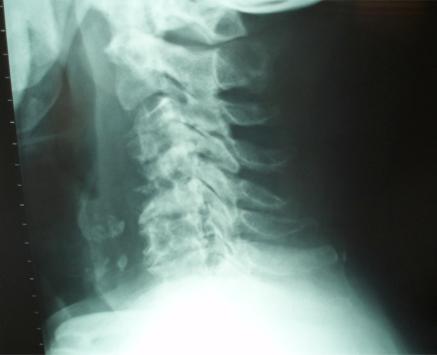

Dialysis-related spondyloarthropathy is a rare cause of spinal deformity and cervical myelopathy. Optimal management of cervical spine spondyloarthropathy often requires circumferential reconstructive surgery, because affected patients typically have both the anterior column and the facet joints compromised. The occasional presence of noncontiguous or "skip lesions" adds an additional level of complexity to surgical management, because decompression and fusion in an isolated segment of neural compression can worsen spine deformity by applying increased stress to adjacent cervical spine segments. We report two cases of hemodialysis patients who presented with cervical myelopathy and initially had anterior cervical discectomy or corpectomy. Because symptoms recurred due to hardware failure, both patients required posterior spine fusion as well. In retrospect, because of the hardware failure, both of these patients might have benefited from a circumferential (combined anterior and posterior) cervical spine reconstruction as their initial treatment.

透析相关性脊柱关节病是脊柱畸形和颈椎脊髓病的罕见病因。颈椎脊柱关节病的最佳治疗通常需要进行环形重建手术,因为受影响的患者通常前柱和小关节均受损。偶尔出现的非连续性或“跳跃性病变”增加了手术治疗的复杂性,因为在孤立的神经受压节段进行减压和融合会因对相邻颈椎节段施加更大压力而加重脊柱畸形。我们报告了两例血液透析患者,他们均表现为颈椎脊髓病,最初接受了颈椎前路椎间盘切除术或椎体次全切除术。由于内固定失败导致症状复发,两名患者均还需要进行后路脊柱融合术。回顾来看,由于内固定失败,这两名患者最初若接受环形(前后联合)颈椎重建术可能会受益。